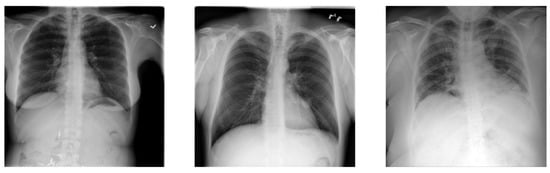

4.2. Dataset

- COVID-19—11,956 samples;

- Non-COVID infections (viral or bacterial pneumonia)—11,263 samples;

- Normal (uninfected)—10,701 samples.